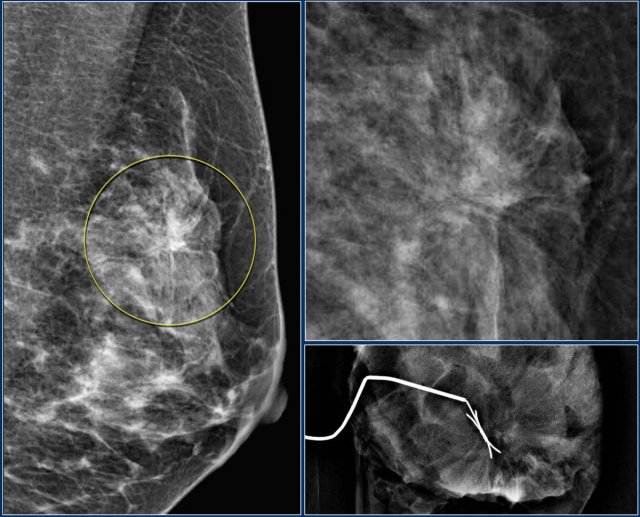

Architectural distortion

The term architectural distortion is used, when the normal architecture is distorted with no definite mass visible.

This includes thin straight lines or spiculations radiating from a point, and focal retraction, distortion or straightening at the edges of the parenchyma.

The differential diagnosis is scar tissue or carcinoma.

Architectural distortion can also be seen as an associated feature.

For instance if there is a mass that causes architectural distortion, the likelihood of malignancy is greater than in the case of a mass without distortion.

Notice the distortion of the normal breast architecture on oblique view (yellow circle) and magnification view.

A resection was performed and only scar tissue was found in the specimen.